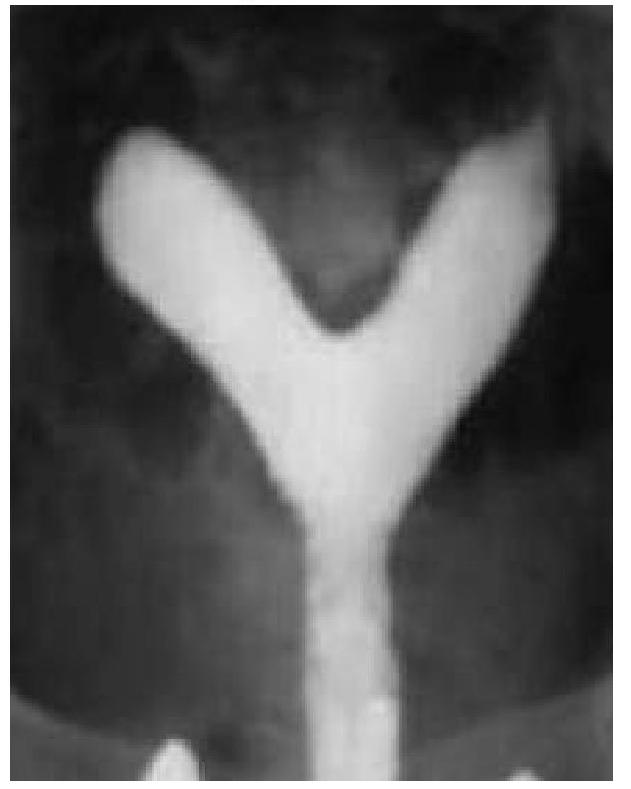

A 20 year old woman is evaluated for primary infertility. Hysterosalpingography was done and reveals an anomaly. What is the anomaly seen in the image?

Explanation: ***Septate uterus*** - The image exhibits a **single uterine cavity** with a **septum** or indentation extending downwards, splitting the cavity into two distinct portions superiorly. - This configuration, particularly with an external contour that is typically **convex or flat**, is characteristic of a septate uterus, which is often associated with recurrent pregnancy loss and infertility. *Uterine didelphys* - This anomaly involves **two completely separate uteri**, each with its own cervix and often a separate vagina. - The image clearly shows a single main uterine body that then divides superiorly, not two entirely distinct uteri. *Bicornuate uterus* - A bicornuate uterus typically has two uterine horns that are **divergent externally**, creating a **deep indentation** on the external contour of the fundus. - While it also involves a divided uterine cavity, the external contour in the image appears more convex or flat, which is less consistent with a bicornuate uterus where the outer fundal contour is notably indented. *Unicornuate uterus* - This anomaly results from the **failure of one Müllerian duct to develop**, leading to a uterus that has only one horn and one fallopian tube. - The image presents a uterus with two distinct horns, ruling out a unicornuate uterus.